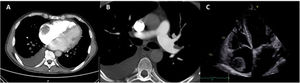

The electrocardiogram showed sinus rhythm with left atrial abnormality and positive electrocardiographic criteria for left ventricular hypertrophy. Computed tomography pulmonary angiography revealed pulmonary embolism (PE), with thrombi in the left segmental and subsegmental branches of the pulmonary artery and a 5-cm right atrial mass suggestive of thrombus (Figure 1A and B).

TTE showed severe mitral regurgitation caused by posterior leaflet prolapse, two mobile right atrial masses measuring 2.4 cm×1.5 cm and 3.6 cm×3.7 cm (Figure 1C), PASP of 70 mmHg, moderate dilatation of the right ventricle, reduced right ventricular function (tricuspid annular plane systolic excursion 16 mm) and preserved left ventricular function.